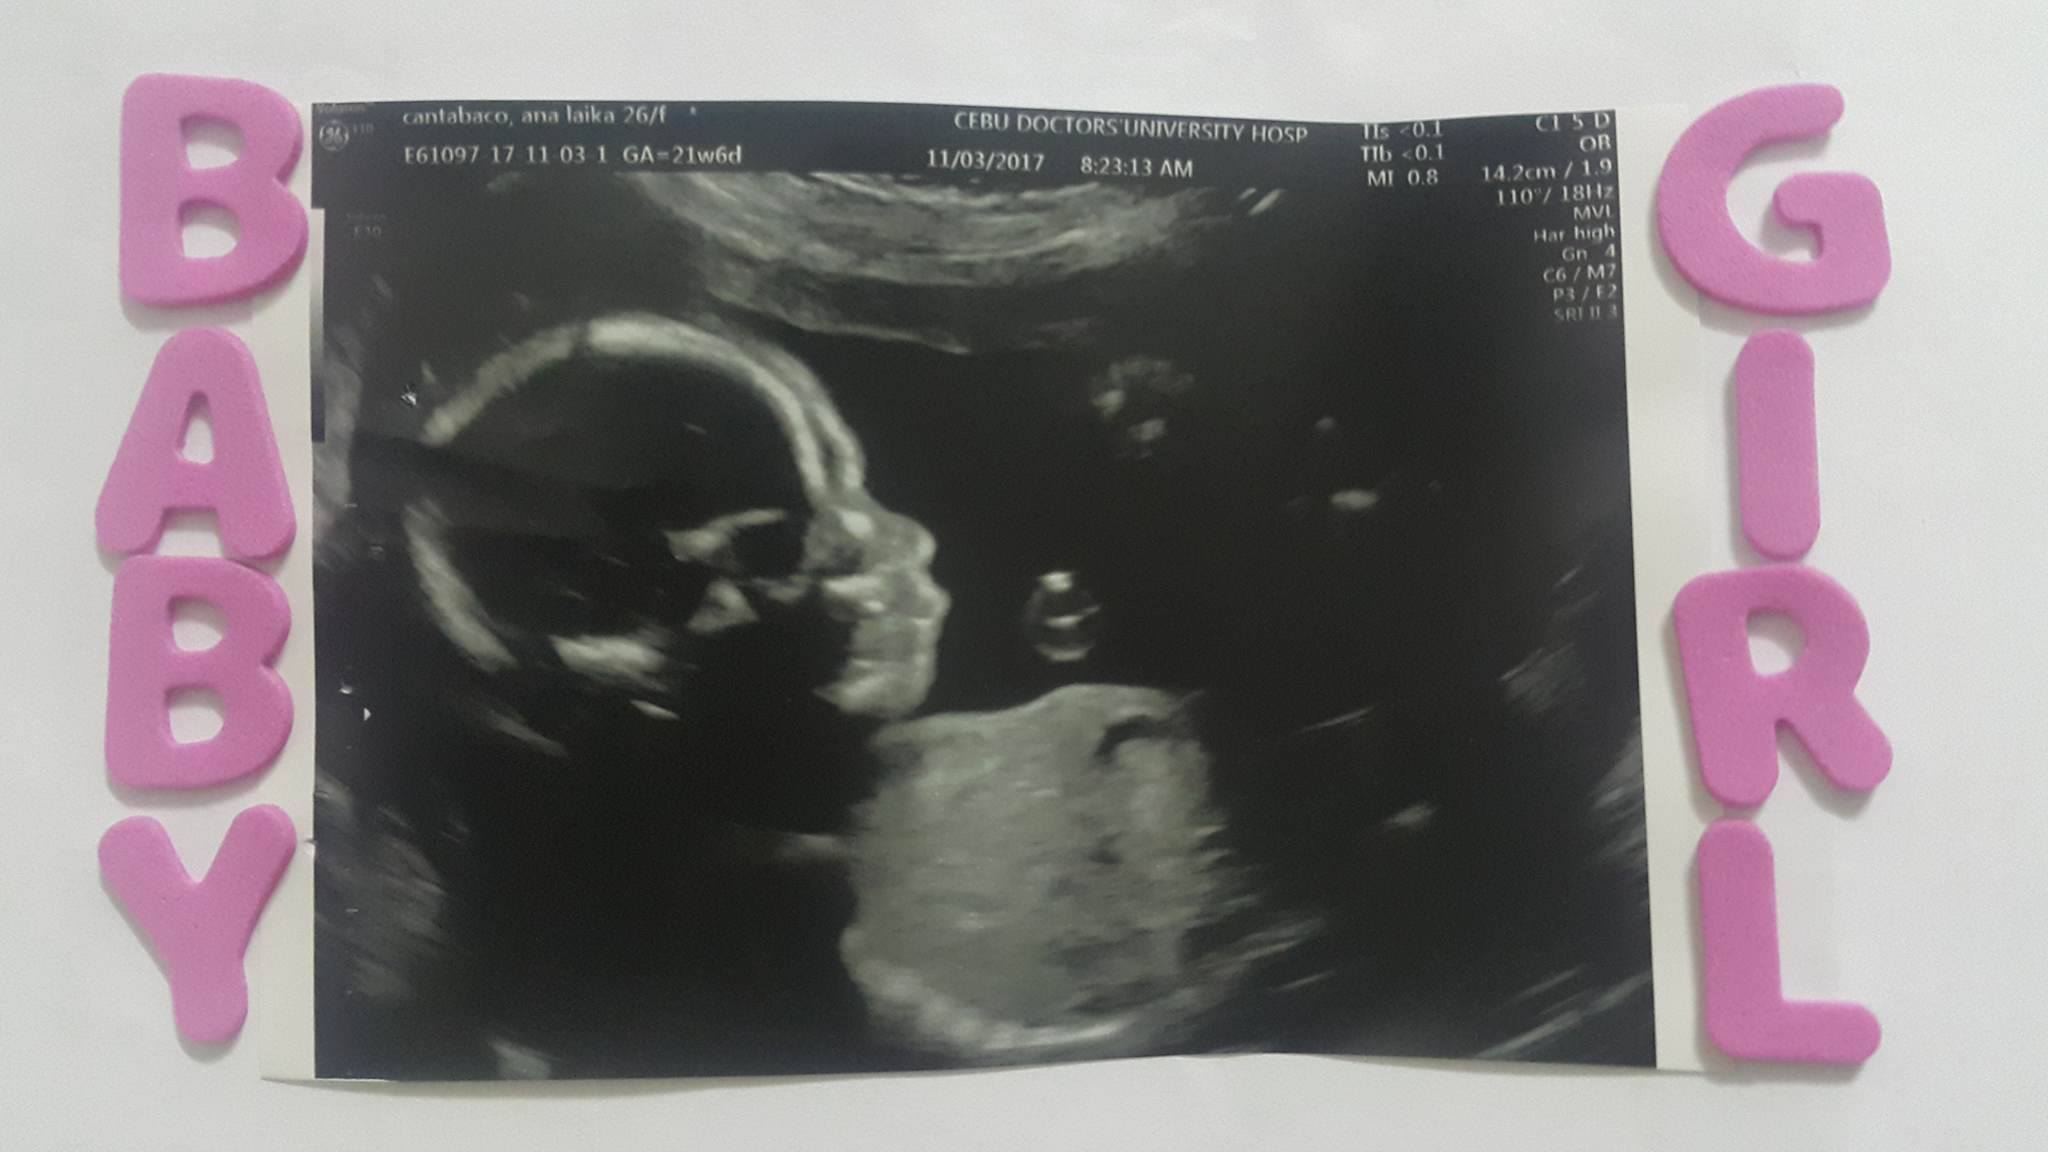

My partner wants to have a baby girl. So we decided to have an ultrasound to check the gender of the baby after 4 months. The time has come and both of us are very excited for the result and Tadaaaaaa! To our surprise, lucky we are because it's a baby girl! Thank you god for always hearing our prayers.